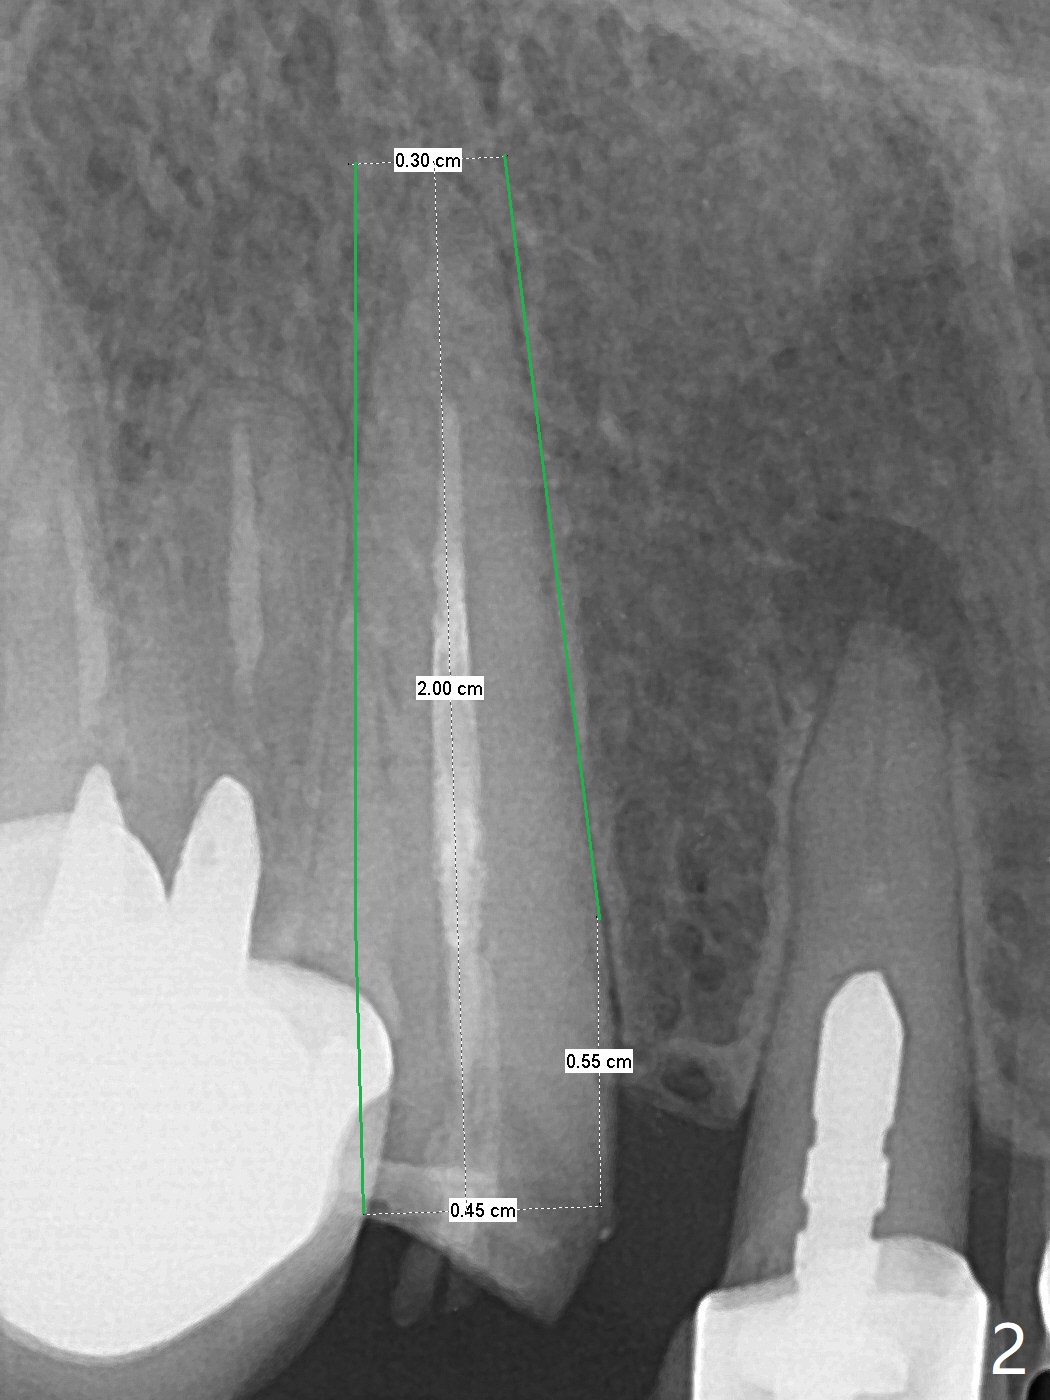

60岁女比较瘦小,8个月前因右下4,5轻度植体周围炎(4.5毫米软组织水平两段式植体种得太颊侧)就诊,准备重做,后来由于口腔卫生改善,症状减轻,她不愿意手术。右下6种植两个2.5x10毫米一段式种植。最近右上尖牙折裂,部分龈下(图一),她果断选择拔除种植。根尖片显示足够空间植入4.5x20毫米软组织水平植体(图二)。8个月前拍摄CT冠状面表明有充分根尖骨质(图三),植入3x14毫米骨水平一段式植体,便有2毫米颊侧,腭侧骨壁(减少植体周围炎可能性),而且修复角度优越(图四)。我可能在腭侧牙槽窝下1/3骨壁垂直钻入,然后改变钻洞方向,如红线,临床上,由咬合关系决定方位。如果不行,我有15度一段式植体。Bendable植体来不及买了。